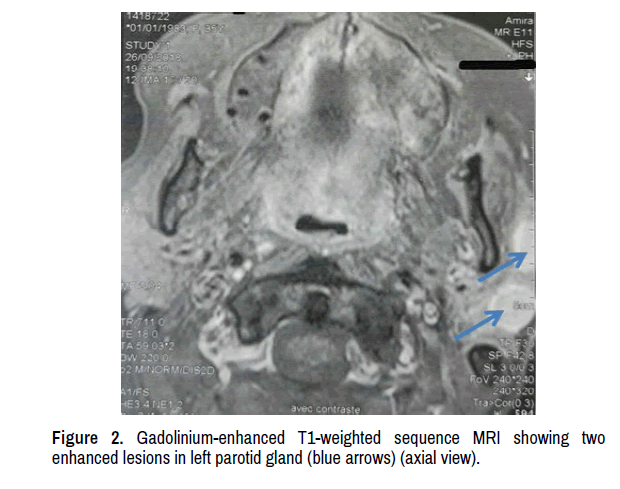

In March 2018, the patient complained of headache and left temporal swelling. This subcutaneous mass was painless and firm. Physical exam was otherwise unremarkable. Head and Neck MRI revealed a left frontal enhancing lesion measuring 23 mm in greatest dimension with limited leptomeningeal enhancement (Figures 1 and 2). Three other enhancing lesions were found in left subcutaneous temporal area (01 mass) and in left parotid gland (02 masses) (Figures 1-3). Brain and spine MRI revealed no additional lesions. Fluorodeoxyglucose positron emission computed tomography FDG PET-CT scan showed pathological uptakes corresponding to subcutaneous and parotid masses. No distant metastases were found.

Figure 2: Gadolinium-enhanced T1-weighted sequence MRI showing two enhanced lesions in left parotid gland (blue arrows) (axial view).